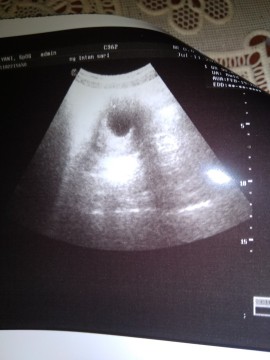

Bunda maaf ingin sharing, hamilku 7 week baru ada kantung dan di dlm kantung baru ada yorkshak (kuning telur) atau makanan si janin. Masalahnya yg makan siapa? Janinku katanya belum ada. Adakah yg 1 pengalaman dgnku bun? Ada yg blg kuning telur itu bakal jadi janin bun. Itu yg saya lingkarin bun kuning telurnya. Klo emg gak ada janinnya aku BO soalnya kata dokternya aku gak mual gitu bun. Gimana ya bun???

Hay bun... Saya kmaren 7 wekk jg masih kantong blm nampak titik sekalipun... Apalagi kehamilan pertama saya BO bun... Udah mikir macam2... Tp alhamdulillah balik lg usg 11 wekk janin nya udah nampak udah ada detak jantung nya... Sekarang usia kehamilan saya 15minggu... Ini usg pas 7 minggu....